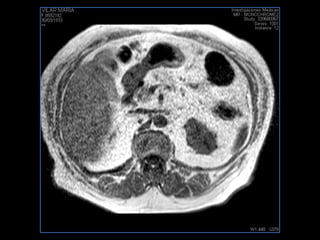

PROTOCOLO hemocromatosis AXIAL supresión grasa /AX multieco en higado COR T2 AX T1 +SAG T2  CON   GADOLINIO :  COR T1+AX T1 SAT: NO  FASE: RL THK: 4MM  COIL:  GAP: (FACTOR 1.4) 1MM FOV: 40 CM NEX:2 SINCRONIZACION RESPIRATORIA EN 3 O 4 CICLOS ALE

PROTOCOLO pancreas/ riñon AXIAL fat sat /AX in phase out phase AX T1 +SAG T2  COR T2, CON   GADOLINIO :  COR T1+AX T1(DIN) SAT: NO  FASE: RL THK: 4MM  COIL:  GAP: (FACTOR 1.4) 1MM FOV: 40 CM NEX:2 SINCRONIZACION RESPIRATORIA EN 3 O 4 CICLOS ALE

resonancia de abdomen